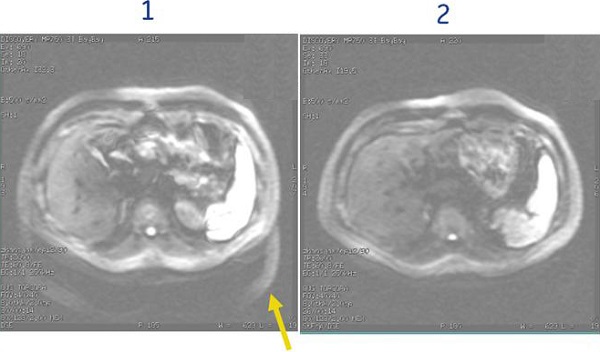

Figure 2. Note reduced chemical shift when SPECIAL is applied to a DWI scan

Table 2. Image legend

NumberDescription

1SPECIAL is turned Off

2SPECIAL is turned On with Auto TI = 110 ms